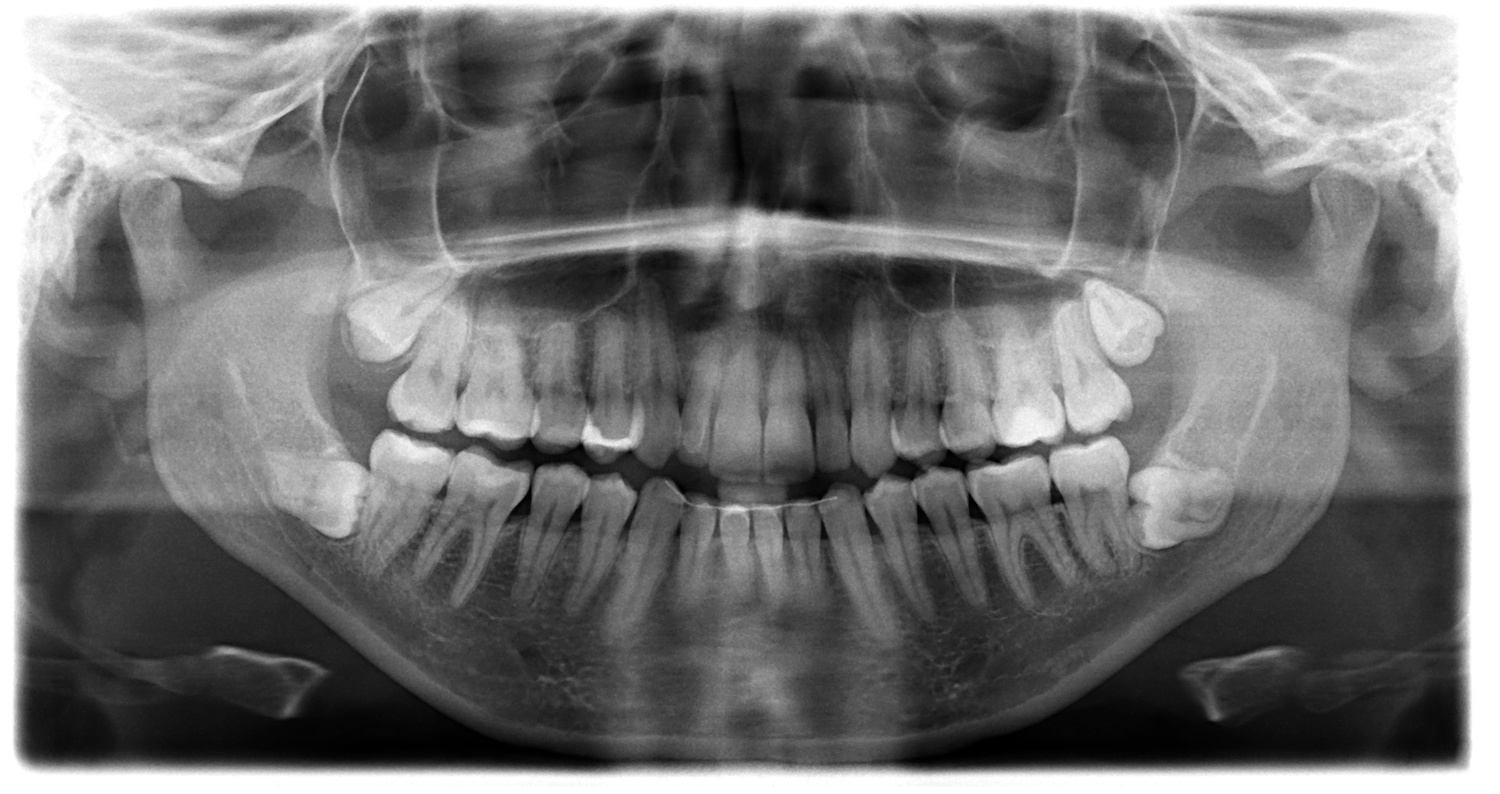

Digital X-rays and 3D imaging are often used to assess positioning and risk accurately.